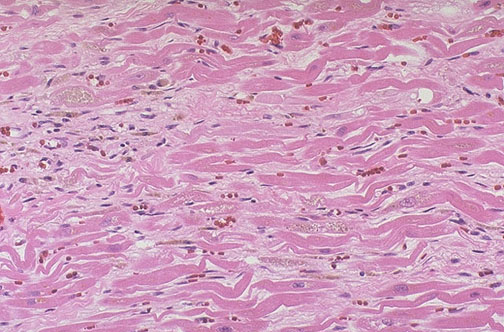

Диффузное повреждение миокарда нарушения

Диффузное повреждение миокарда нарушения 118 фото